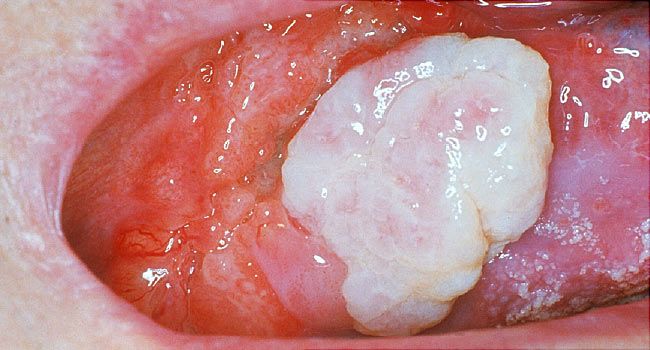

What Does Mouth Cancer Look Like 5 Pictures Of Mouth Cancer

Visual Guide To Oral Cancer

Oral Cancer Images The Oral Cancer Foundation

Oral Cancer Images The Oral Cancer Foundation